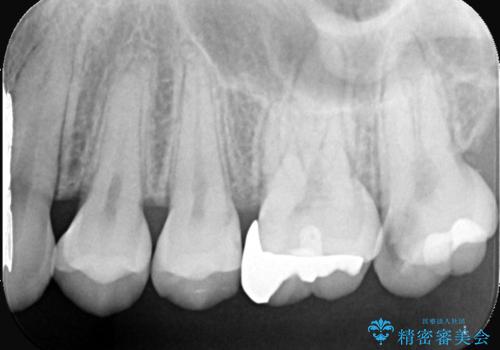

- 「冷たいものが強くしみる」という主訴でご来院されました。精密な診査の結果、虫歯が非常に深く、通常であれば神経を全て抜く「抜髄(ばつずい)」が必要な状態でした。しかし、神経を抜くと歯の寿命が縮まってしまうため、今回は神経の一部を温存する**「部分的断髄法(VPT)」**を提案しました。高い殺菌性と封鎖性、そして組織の再生を促す効果を持つMTAセメントを使用して神経を保護し、最終的には強度と審美性に優れたセラミックで修復する計画を立案しました。

部分的断髄法(MTAの使用): ラバーダム防湿を行い、無菌的な環境下で虫歯を慎重に除去。神経の露出を確認した後、炎症を起こしている一部の神経のみを除去し、残りの健全な神経を保護するためにMTAセメントを充填しました。これにより、神経の機能を維持し、歯を内部から守ることが可能となりました。